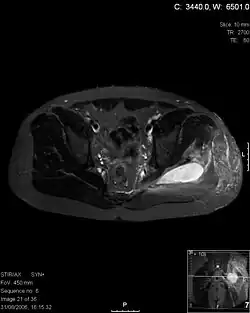

Transverse T2 magnetic resonance imaging section through the hip region showing abscess collection in a patient with pyomyositis.